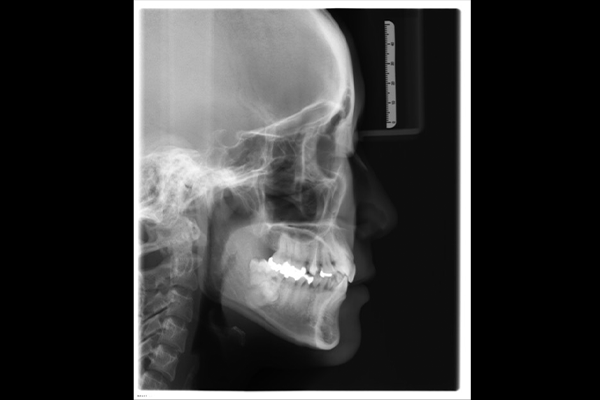

2.レントゲン検査

(パノラマ・セファロ)

矯正診断で特に重要なのがレントゲン検査です。

⚫︎セファロX線(頭部X線規格写真)

顎の骨格の大きさやズレ、上下顎の位置関係、成長方向を分析するために必須の検査です。

これらのデータは、矯正治療の「設計図」となる重要な役割を果たします。